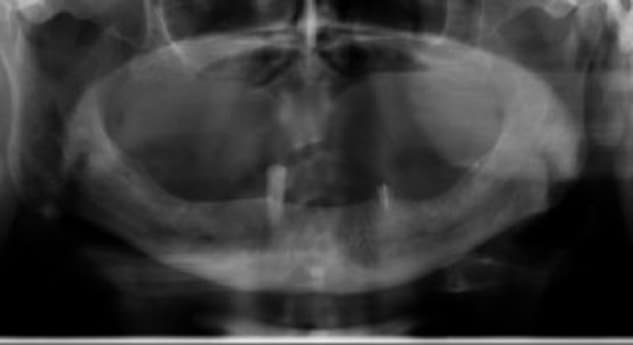

A 73-year-old female patient with long-standing type II diabetes mellitus (average glucose level ≈ 200 mg/dL) presented with edentulism of the lower jaw and poor bone quality, classified as D4 bone - characterized by thin cortical plates and sparse trabecular bone. Seven implants were placed immediately after extractions, each equipped with a MED healing abutment to enhance bone metabolism and accelerate osseointegration, addressing the impaired healing potential typically associated with diabetic conditions.

Despite the compromised systemic condition and low bone density, the healing process was remarkably successful. Within less than three months, complete osseointegration was achieved across all seven implants, enabling delivery of the final prosthetic restoration. The use of MED healing abutments significantly improved local bone response, stabilized the peri-implant tissues, and facilitated rapid and predictable rehabilitation in a high-risk diabetic patient with D4 bone quality.